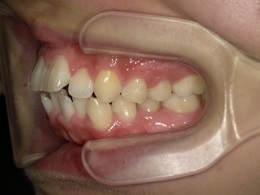

治療前左側

治療後左側

治療前右側

右側治療後